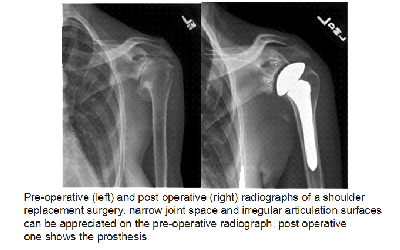

Shoulder joint replacement (arthroplasty): Advanced arthritis of the glenohumeral joint can be treated with shoulder replacement surgery, in which the damaged parts of the shoulder are removed and replaced with artificial components, called a prosthesis.

There are many types of replacement surgery of the shoulder:

Hemiarthroplasty. Just the head of the humerus is replaced by an artificial component.

Total shoulder arthroplasty. Both the head of the humerus and the glenoid are replaced. A plastic “cup” is fitted into the glenoid, and a metal “ball” is attached to the top of the humerus.

Reverse total shoulder arthroplasty. In a reverse total shoulder replacement, the socket and metal ball are opposite a conventional total shoulder arthroplasty. The metal ball is fixed to the glenoid and the plastic cup is fixed to the upper end of the humerus. A reverse total shoulder replacement works better for people with cuff tear arthropathy because it relies on different muscles — not the rotator cuff — to move the arm.

Recovery: Surgical treatment of arthritis of the shoulder is generally very effective in reducing pain and restoring motion. Recovery time and rehabilitation plans depend upon the type of surgery performed. You will generally spend a 2-3 weeks in an arm pouch following surgery, to rest your shoulder, following which rehabilitation exercises are started. Please discuss these with your surgeon.